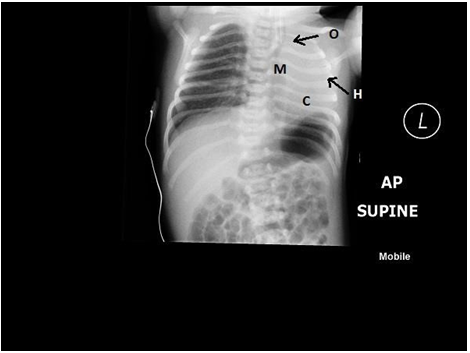

This was a term male baby, born with 2.9 KG weight. Ante natal scan at 36 week had shown evidence of polyhydramnios. Soon after birth, an NGT passed failed to pass into the stomach, confirming the diagnosis of esophageal atresia and the baby was shifted to NICU. A chest Xray was ordered on arrival in NICU and this showed hyperinflated Left lung with absent lung markings on the right side. The heart and mediastinum were grossly shifted to the right with a diagnosis of right lung agenesis, a contrast enhanced CT scan was done. This confirmed a Type 1 pulmonary agenesis with complete agenesis of Rt lung and Rt pulmonary artery and bronchus.

The baby underwent a primary single stage repair of esophageal atresia through a Rt thoracotomy, successfully. Oral feeds were commenced on day 7, after a contrast study confirmed an intact anastomosis. The child is alive and well at 4 years of age.